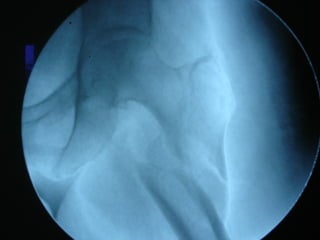

Tc pre op

frattura

TC RMN

Rx post